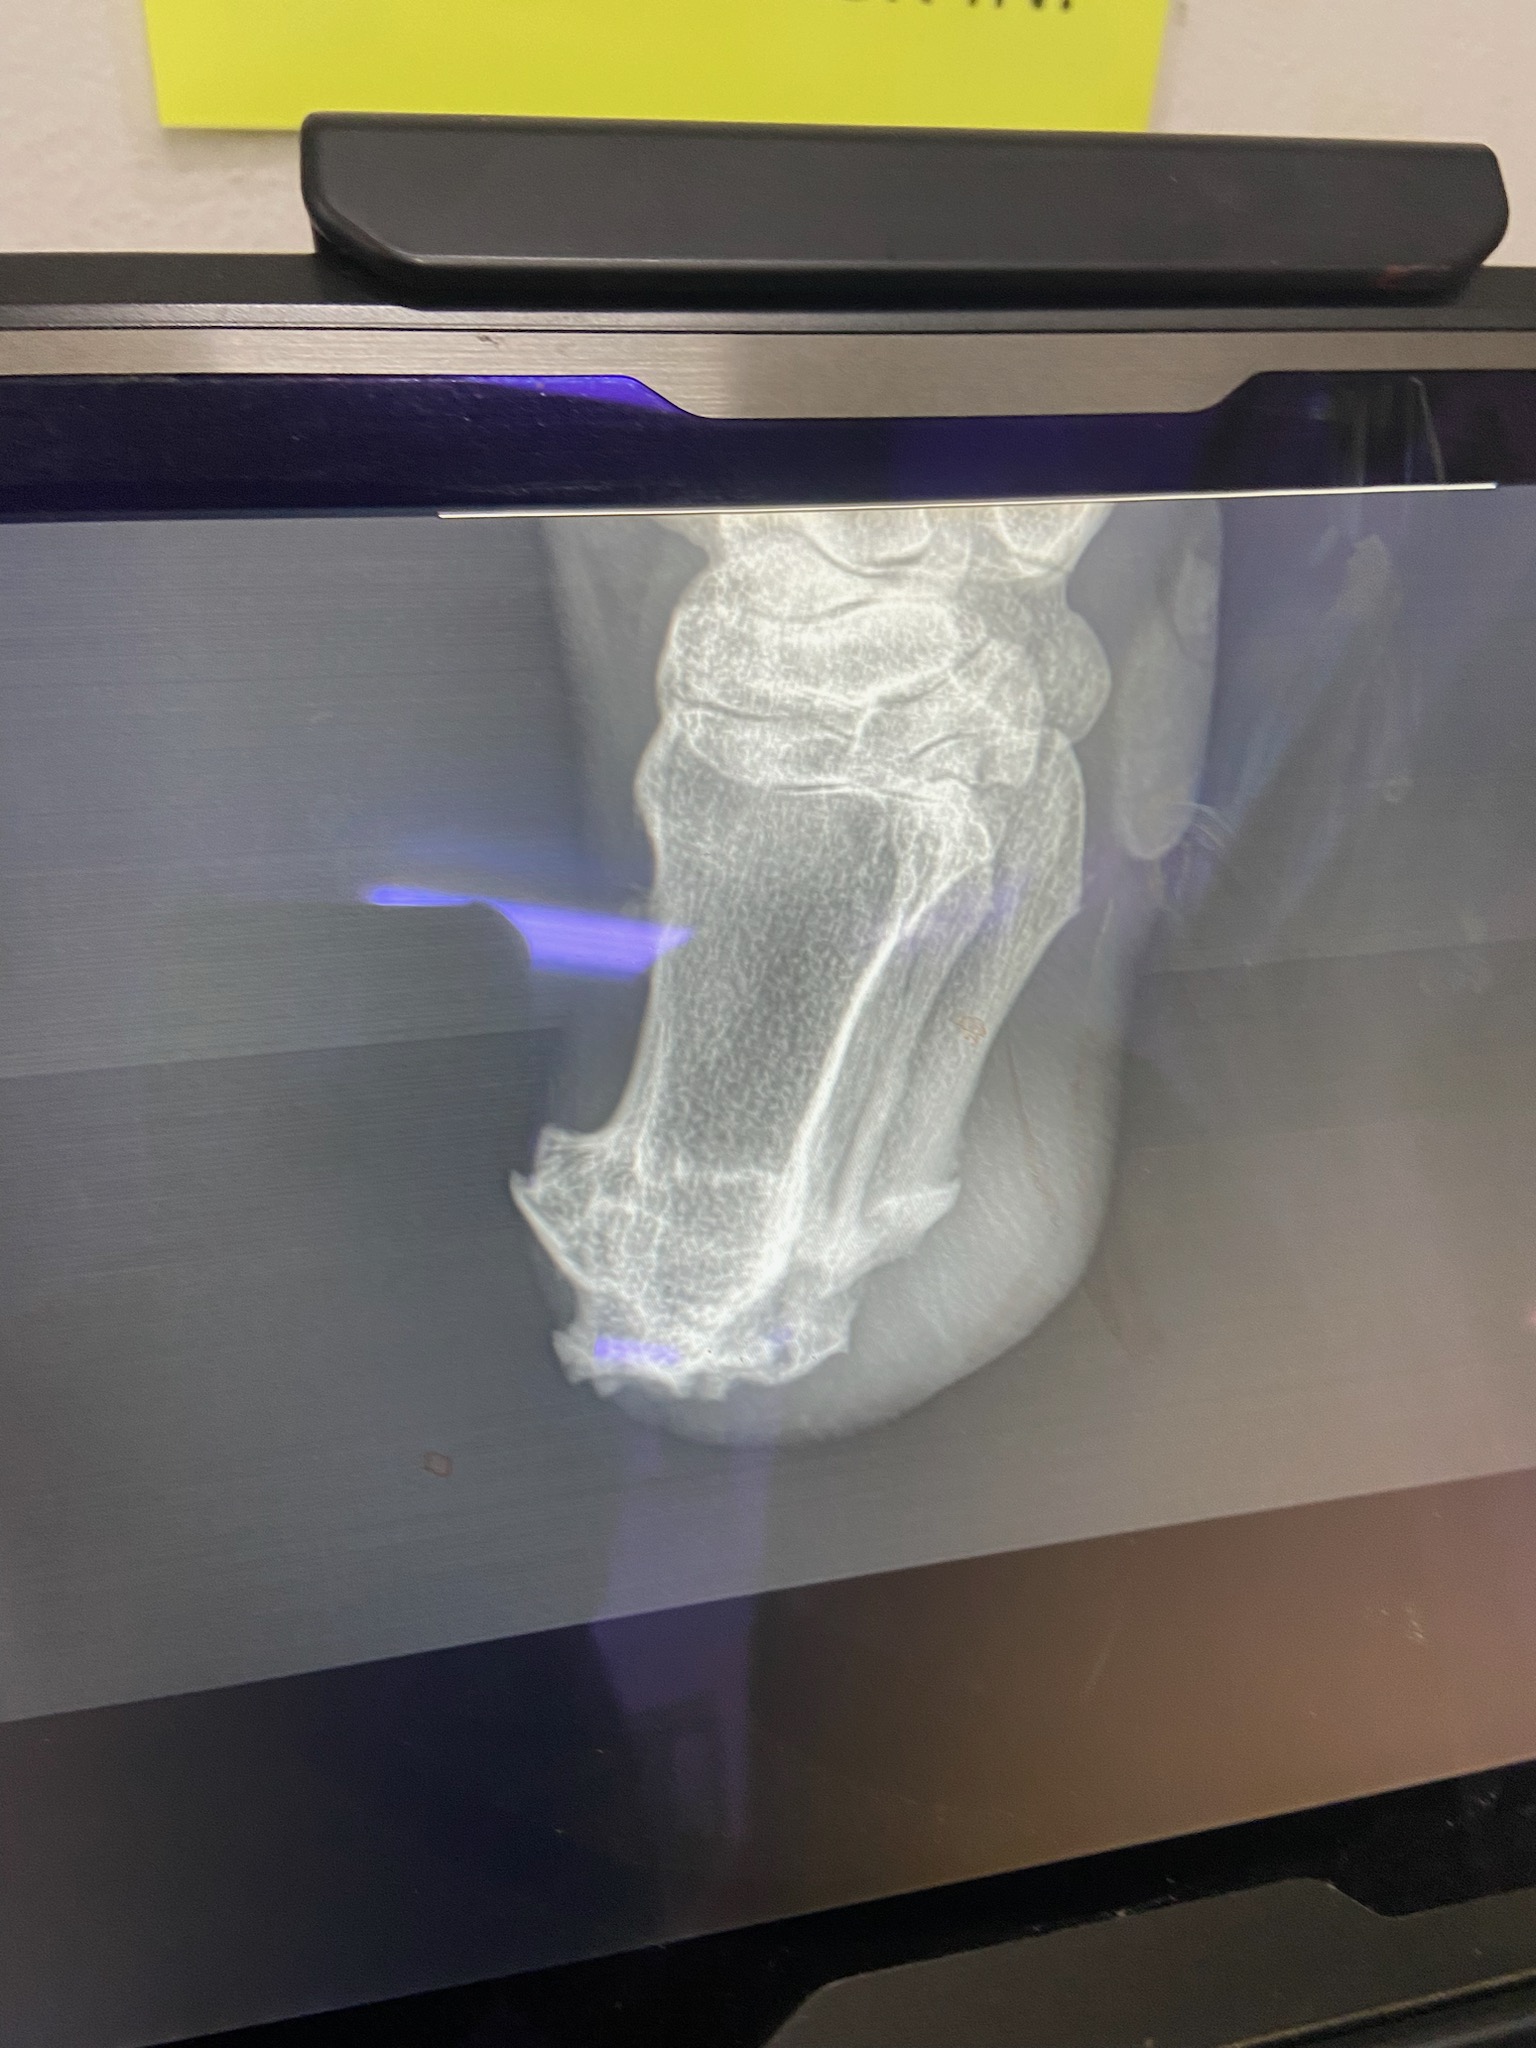

Lieutenant Dan is a 2020 miniature stallion who came to us from a January 2025 Carlton County case. He is MISSING the lower part of his left hind leg and has been living this way for at least a couple of years. We started his care by doing complete discovery vetting to determine the best way to proceed (a prosthetic specialist is included in the process) in order to provide him with the most humane care possible and to do what is in his best interest. He was sedated, radiographed, and his leg stump was bandaged for protection after a cast was made of it to make a prosthetic. He also had blood pulled for a general workup and Coggin’s testing. The big news to come out of the exam is the fact that he has bullet fragments in one of his front legs (seen on radiographs) which makes us suspect that this may be related to his missing hind leg as well. This little guy is truly a survivor! Thank you so much to everyone at Anoka Equine Veterinary Services for taking such an interest in Lt. Dan’s case and helping to make sure he receives what he needs with their excellent care. His comfort is our main concern and so far he seems to be doing quite well with his prosthetic.